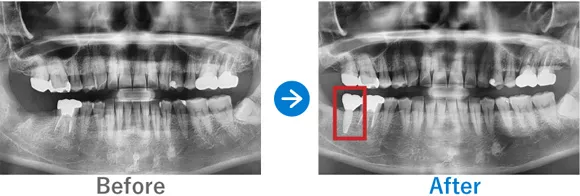

Case3

膿が溜まった奥歯を抜歯しインプラントに。埋もれていた親知らずも抜歯

右下6に歯根嚢胞あり、かかりつけ医院で抜歯が必要と診断

インプラント1本:右下6、抜歯ソケットプリザベーション

495,000円(内訳:抜歯ソケットプリザベーション、インプラント1本(ストローマン)、ガイド、仮歯、保証20年)

来院の背景

右下の治療済みの歯の根っこに膿が溜まり、かかりつけの歯科医院で抜歯が必要と言われて来院されました。

治療結果

歯根の先端に膿ができており、骨吸収が大きい状態でした。そこで、抜歯時に膿をきれいに取り除いたうえで骨補填を行いました。抜歯ソケットプリザベーションからインプラントを行うことにより、歯茎が痩せることなくインプラントを埋入できました。患者様からは、しっかりと噛めるようになったと喜んでいただきました。また、インプラントに加えて埋伏していた親知らずの抜歯も行いました。